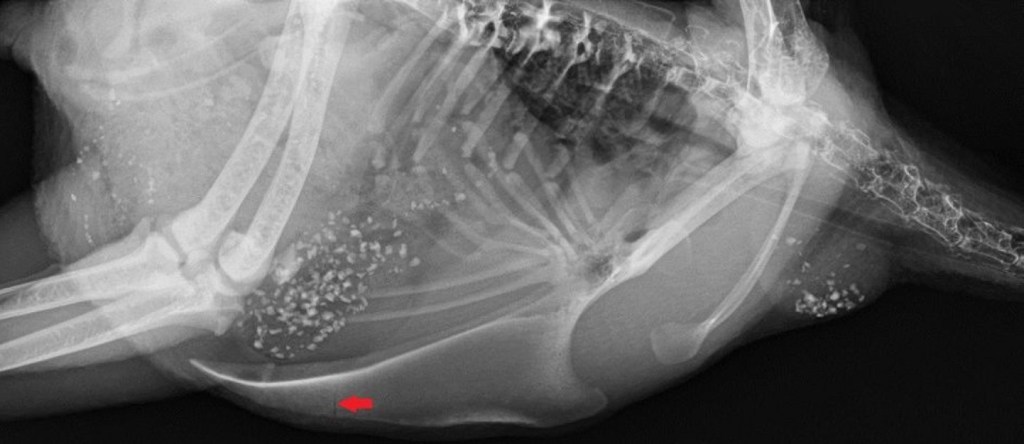

- Osteoporosis: Egg shells are made of calcium which hens draw from reserves in their leg bones. Constant laying, coupled with inadequate sources of dietary calcium, can lead to the loss of bone calcium, weakened legs, stress fractures and osteoporosis.

- Keel Bone Fractures: The growth of a laying hen’s skeletal frame ceases around sexual maturity (approximately 18 weeks of age), but the bone formation process of the keel (breast bone) continues for another five months. When young hens begin producing eggs, the tip of the keel is made of cartilage and not bone. In high-producing layers their keel bone receives inadequate calcium for proper bone growth during the early laying period. A study from the University of Copenhagen revealed that the majority of commercial Danish layers suffer from keel bone fractures, which are the result of disproportionately large eggs that put internal stress on a hen’s skeletal system.